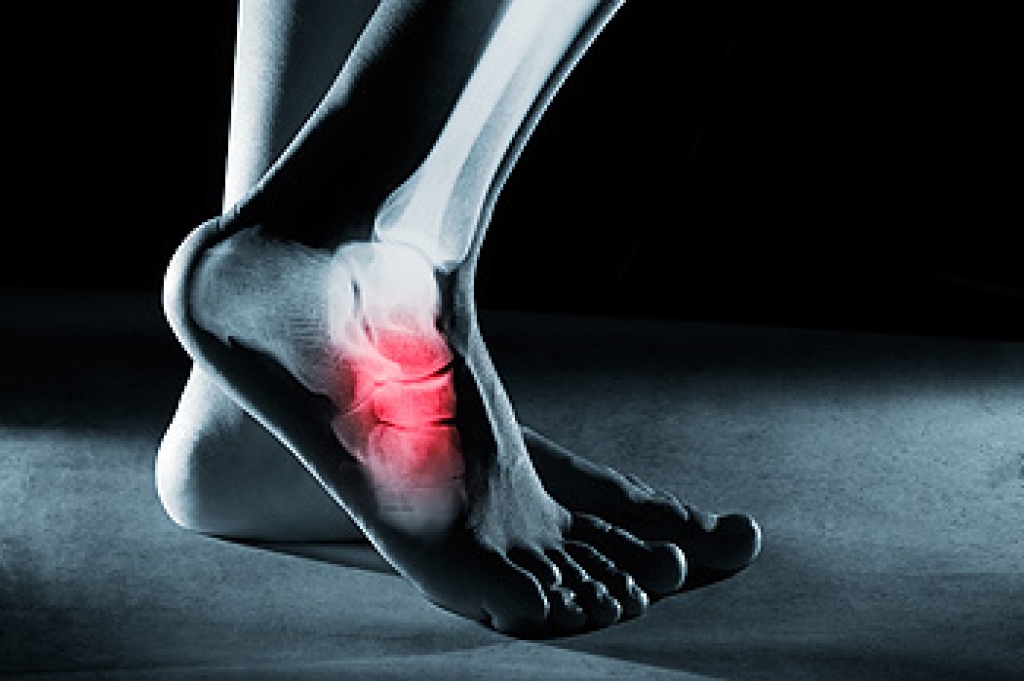

Tarsal tunnel syndrome occurs when a major nerve on the inside of the ankle becomes compressed as it travels into the foot. This pressure can create tingling, burning, numbness, or sharp discomfort that may radiate into the arch, heel, or toes. Symptoms often feel worse after long periods of standing or walking, and some people notice relief only when they rest. Because the nerve sits in a tight space surrounded by ligaments and bone, anything that increases swelling or strain in the area can trigger irritation, including flat feet, prior injury, or certain medical conditions. Ignoring these sensations can lead to ongoing instability or increasing sensitivity in the foot. Early care focuses on reducing pressure, improving support, and calming inflammation to protect the nerve. If the tingling or burning continues or begins to affect your daily routine, it is suggested that you see a podiatrist for an accurate diagnosis and targeted treatment.

Tarsal tunnel syndrome, which can also be called tibial nerve dysfunction, is an uncommon condition of misfiring peripheral nerves in the foot. The tibial nerve is the peripheral nerve in the leg responsible for sensation and movement of the foot and calf muscles. In tarsal tunnel syndrome, the tibial nerve is damaged, causing problems with movement and feeling in the foot of the affected leg.

- Different sensations, an afflicted person may experience pain, tingling, burning or other unusual sensations in the foot of the affected leg.